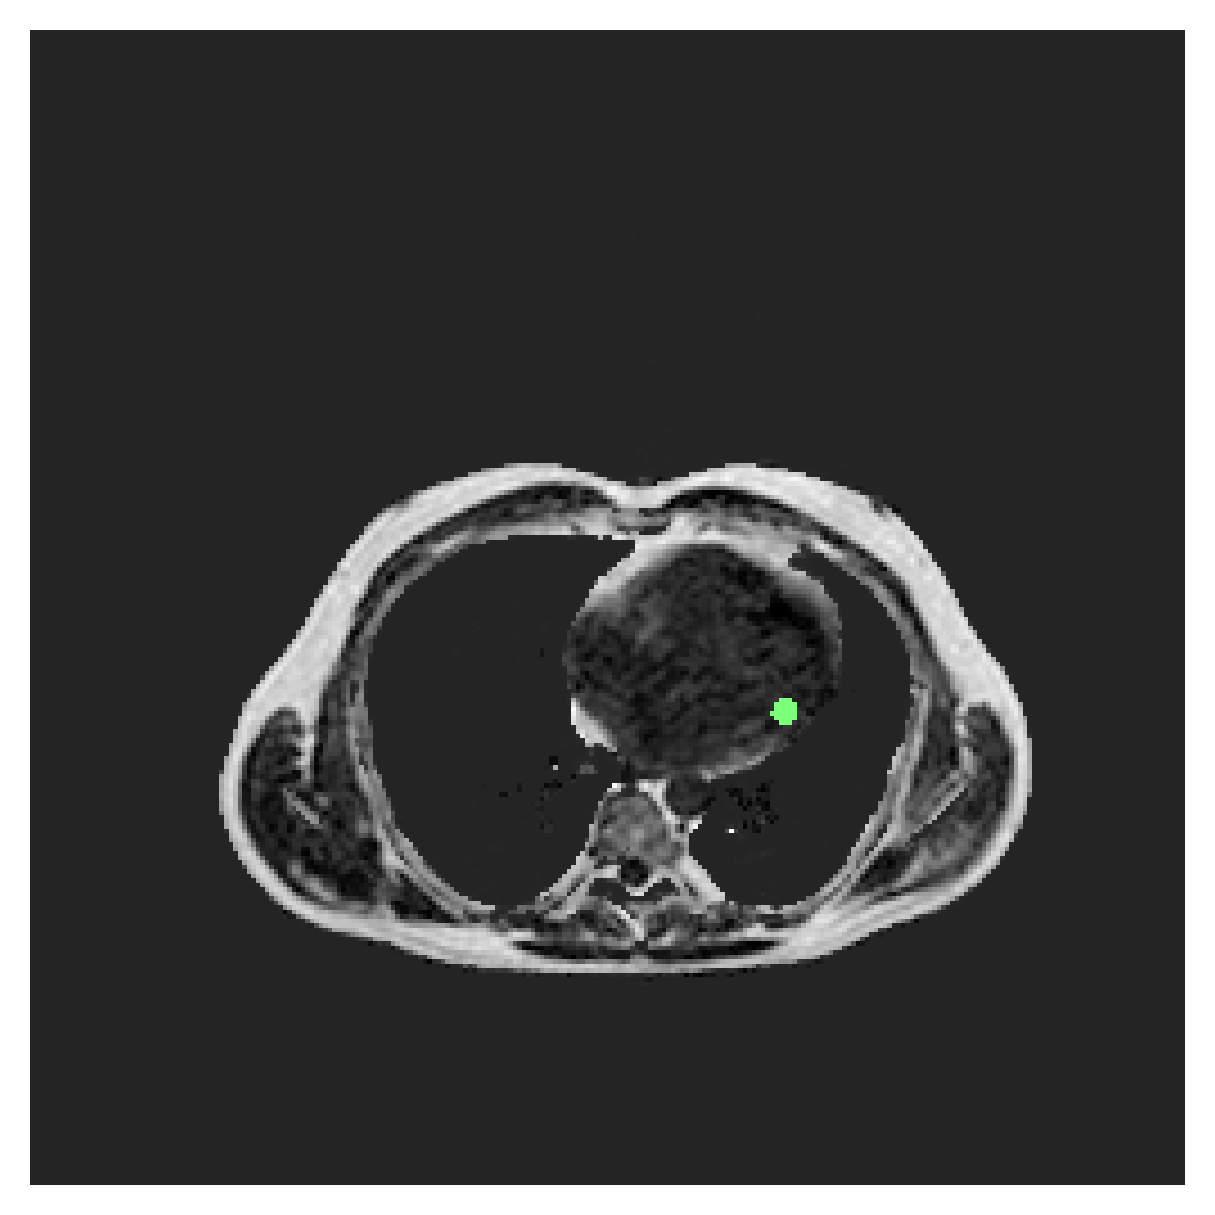

We normalize the volumes and resize the slices to pixels. As the official dataset comes with full annotations, we create a synthetic point ground truth. This is done by first randomly choosing the centers of the point annotations within the class masks, followed by filling an ellipse with axes lengths of and (in pixels) around each center. The intersections of these elliptic discs with the underlying full annotations are then used as our point ground truth. See Figure 2 for an example of the created weak annotation mask. The point annotations are created for every slice, one for each foreground object present in the slice.

5.1 Segmentation of cardiac structures

The average 3D Dice scores and HD95 values on the ACDC test set are given in Table 2, and boxplots in figures 4 and 5 show the distributions. We see that, in terms of DSC, the proposed strategy of using intensity-aware distances withing boundary loss performs better than simply using the Euclidean distance, with the best results achieved by using the strictly intensity based MBD. The HD95 however favors the original version of , which may be do to its smoother predictions and less fragmentation and oversegmentation. The CRF-loss results are significantly worse in both metrics.

In Figure 3 we show the 3D DSC validation curve evolution for a single run. The CRF-loss seems to have converged to a low DSC value, while all settings combining CE and boundary loss reach values close to the full supervision in the beginning of the training and then slowly collapse towards to the point annotations. The MBD version stands out, degrading slower, thus providing a wider range of potentially good models for evaluation.

Qualitative comparison

In Figure 6 we provide qualitative results on a number of randomly chosen test set slices. Upon visual inspection, we can observe that training with the intensity-aware distances (particularly with and ) follows the image gradients better and is better at recovering the underlying shape than the Euclidean version. The CRF-loss seems to recover the shape of the myocardium and left ventricle to some extent, but fails entirely on the right ventricle.